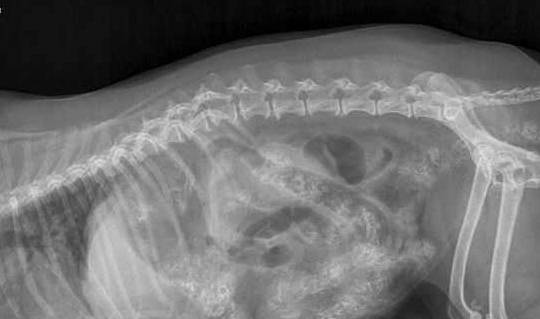

兽医为Jilly照了X光后发现 , 罪魁祸首原来是鸭骨头的碎片 , 它阻塞了狗狗的肠道 。 那时的Jilly已经十分虚弱了 , 兽医们只能采取手术治疗 , 尝试着挽救它的生命 。